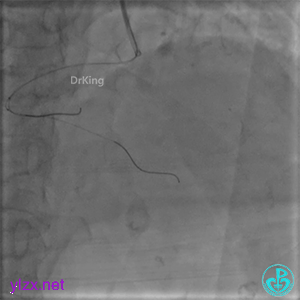

PL远端血管周围似乎有片状造影剂滞留。

经微导管PL分支造影,该如何解读这个经微导管造影结果?

经指引导管造影。

经微导管造影。

远段造影剂外渗在增加,怎么办?